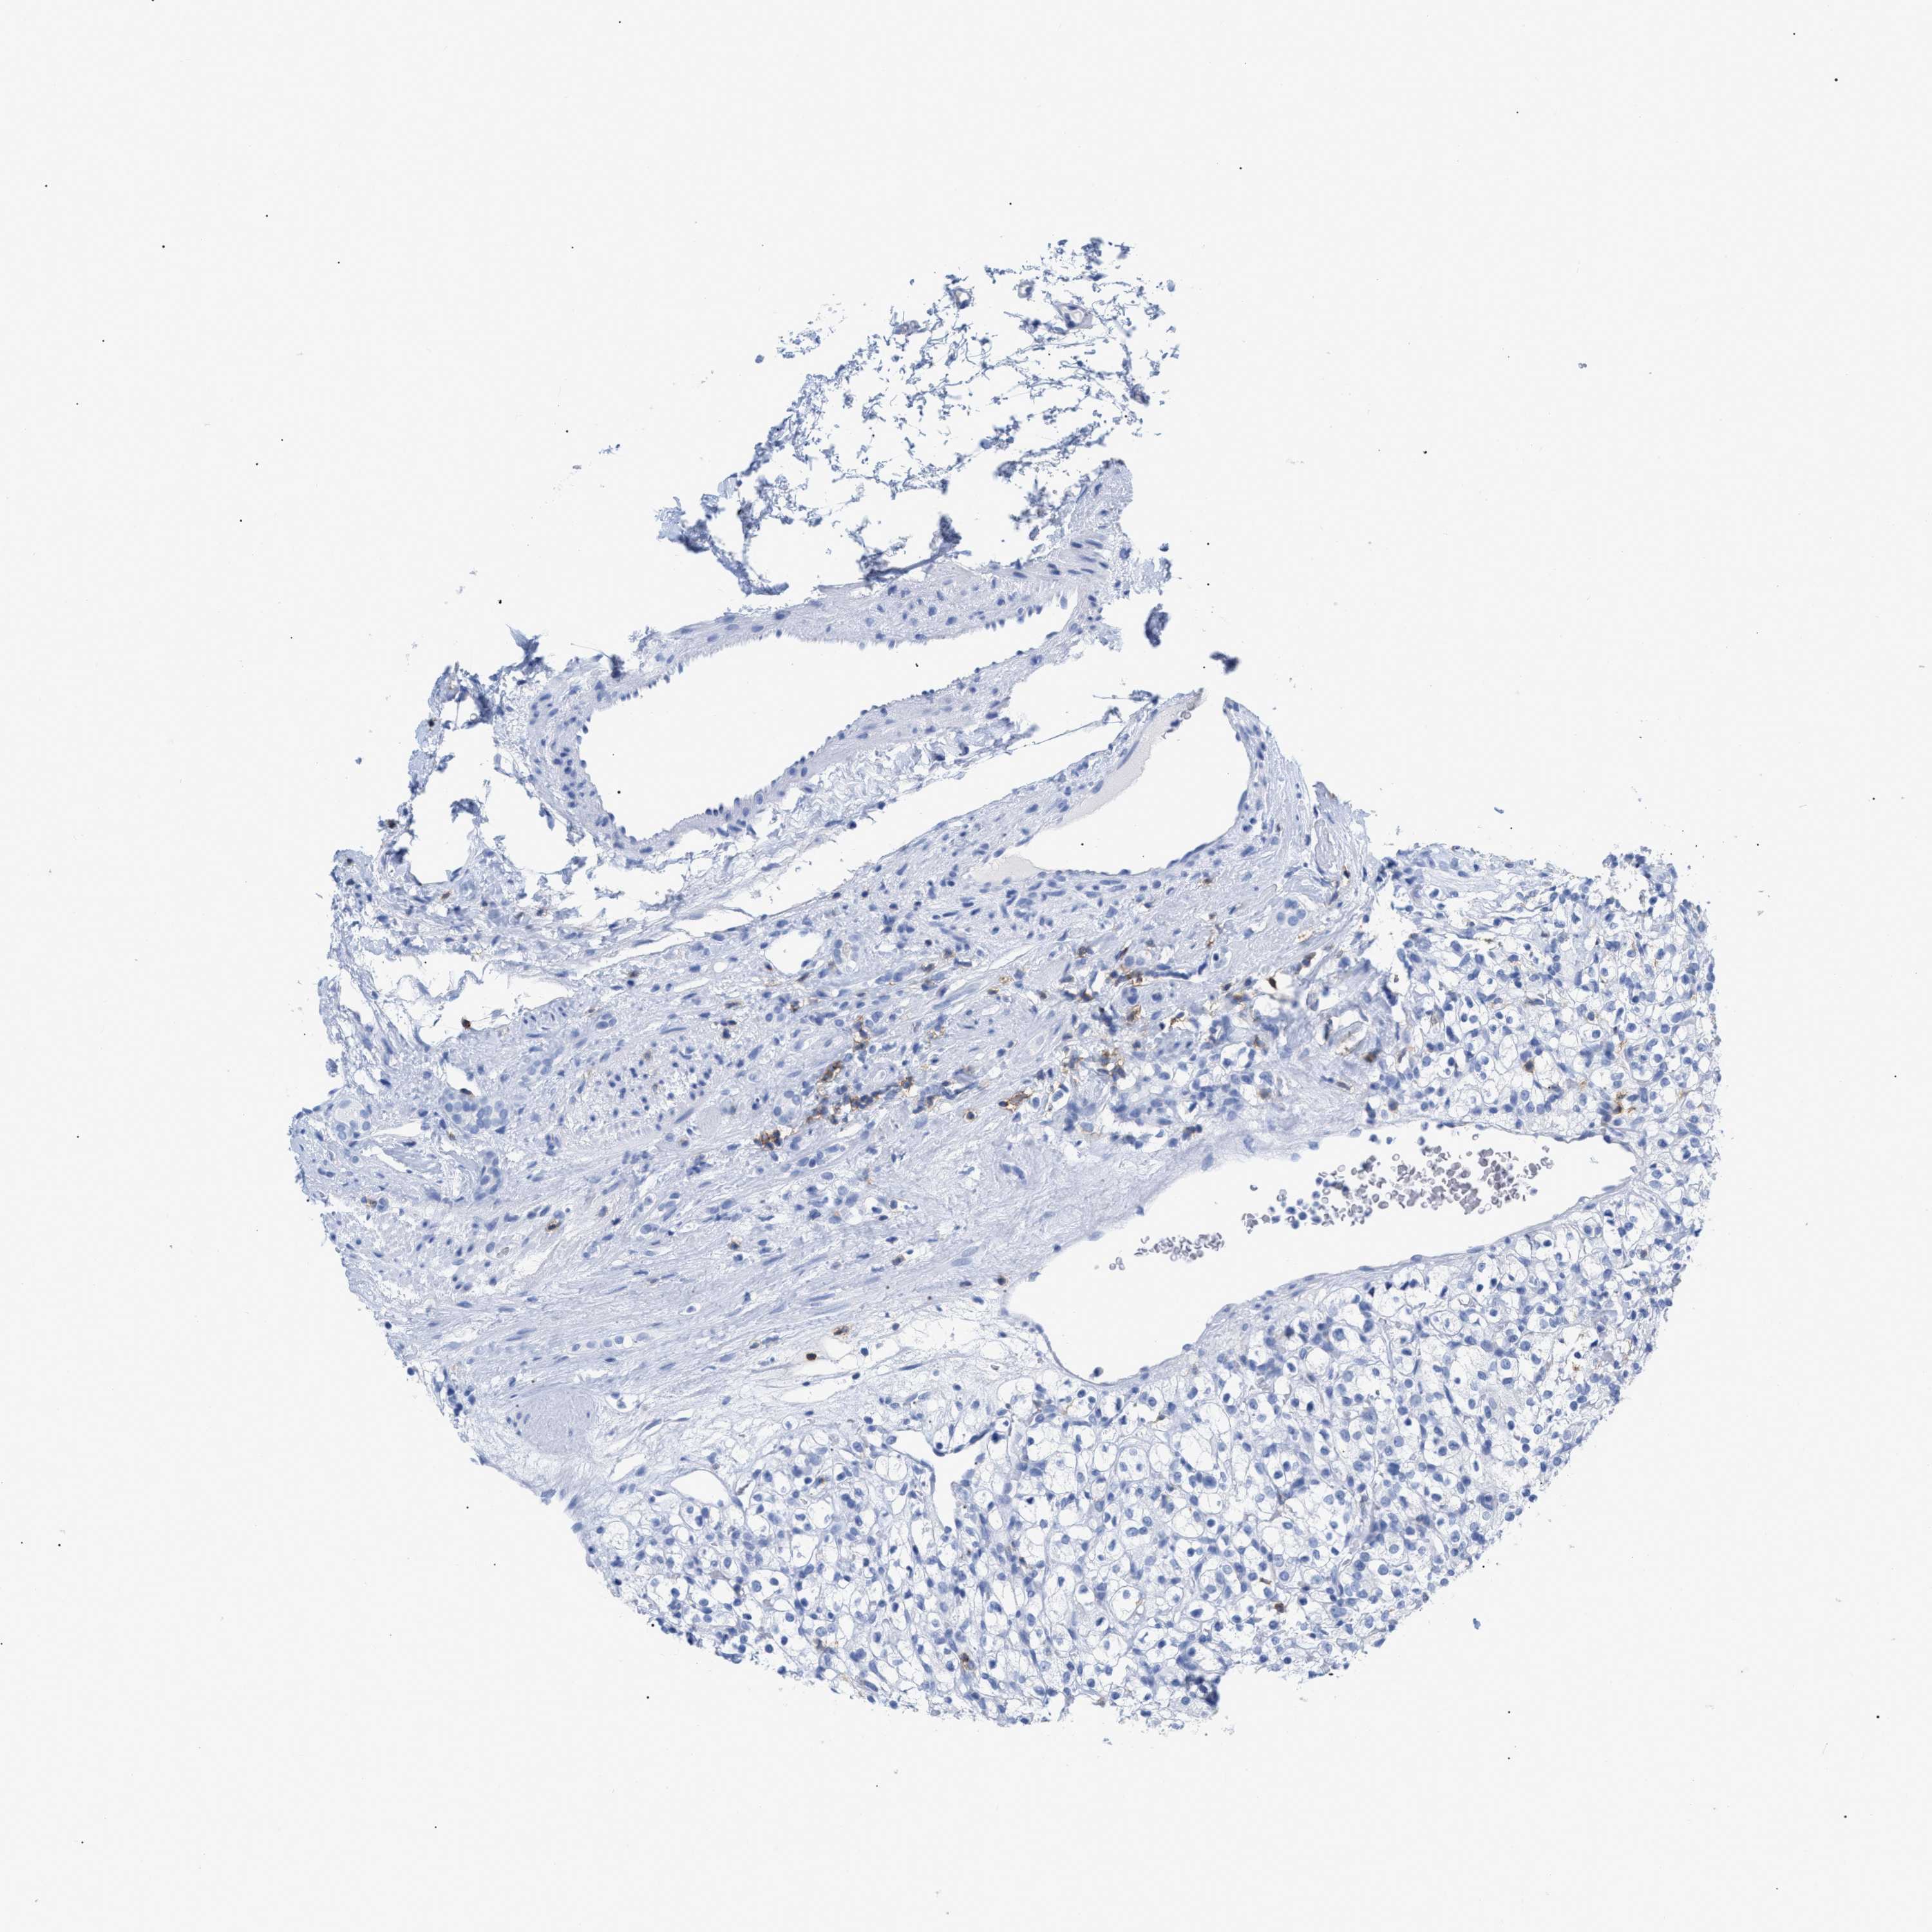

CANCER RENAL CANCER Show tissue menu

KICH TCGA KIRC TCGA KIRC VALIDATION KIRP TCGA PROTEIN RCC CPTAC PROTEIN EXPRESSION

CD5 is not prognostic in Kidney Chromophobe (TCGA)

Average pTPM 0.8

Number of samples 64